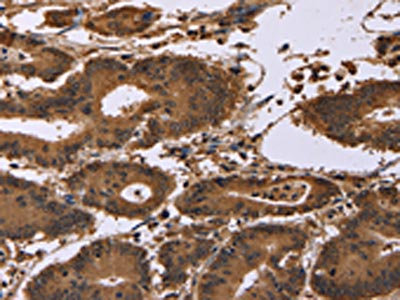

The image on the left is immunohistochemistry of paraffin-embedded Human cervical cancer tissue using CSB-PA161267(EDN2 Antibody) at dilution 1/30, on the right is treated with fusion protein. (Original magnification: ×200)

The image on the left is immunohistochemistry of paraffin-embedded Human colon cancer tissue using CSB-PA161267(EDN2 Antibody) at dilution 1/30, on the right is treated with fusion protein. (Original magnification: ×200)